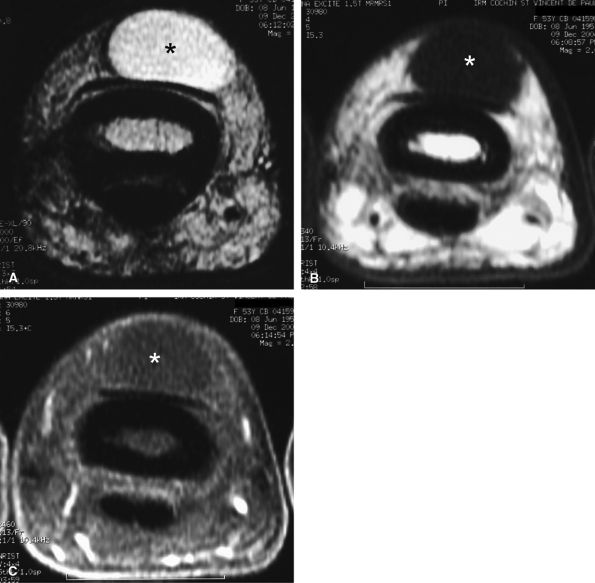

FIGURE 11.70 ● Chondromatosis of the sheath of the flexor tendons on (A) an axial fast spin-echo T2-weighted image and T1-weighted images before (B) and after (C) injection of gadolinium with fat suppression. There is enlargement of the tendon sheaths of the third and fourth fingers with synovitis (arrows) and cartilage signal characteristics (asterisks). (D) Surgical exposure indicating white cartilage nodules (asterisks).